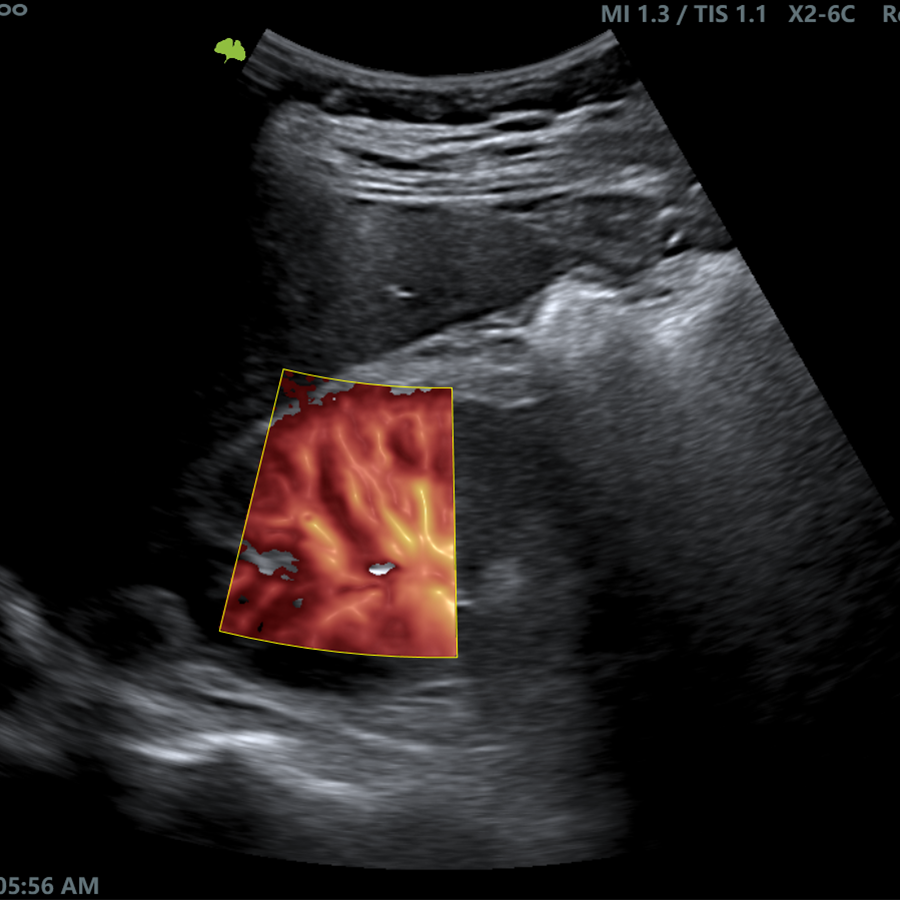

Radiología

- Pview

- TView

- Elastografía Semicuantitativa

- Needle Enhancement

- Guía de Biopsia

- VFlow+

- Doppler 3D

- IMT en Tiempo Real